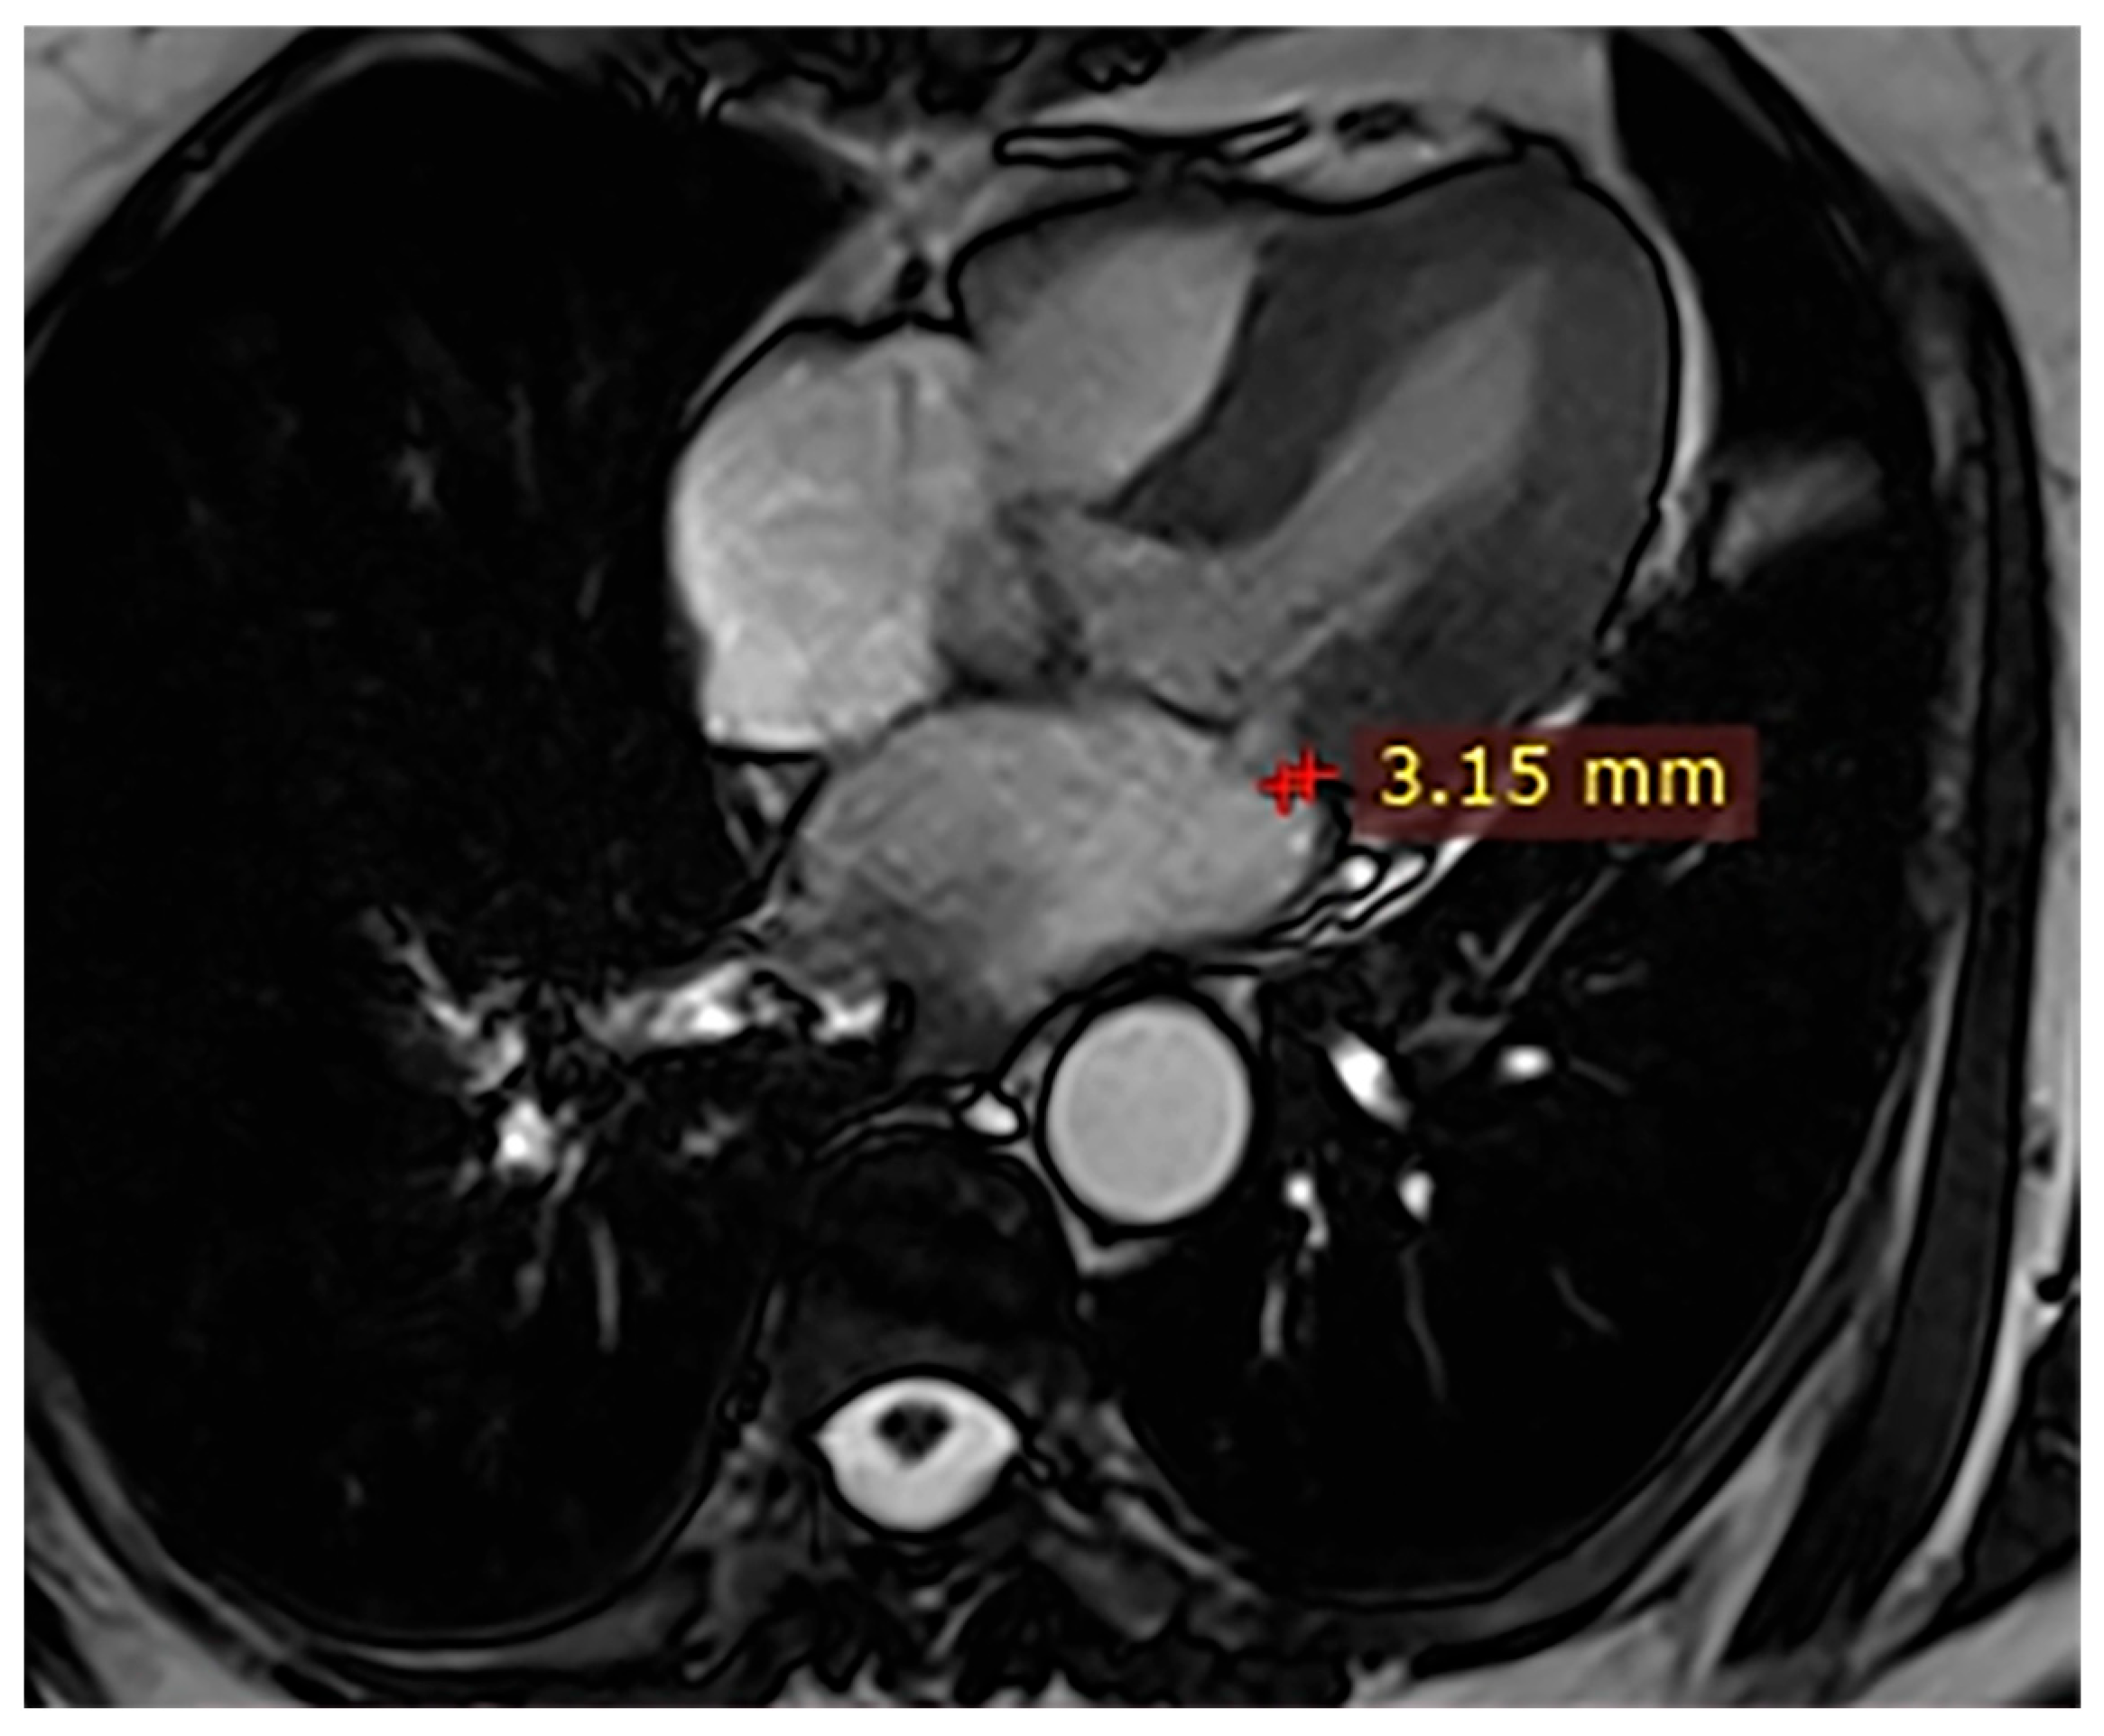

| Case | Patient (Sex, Age) | Symptoms | MAD (mm) | Valvular Issues | LGE | Other Details |

|---|---|---|---|---|---|---|

| 3 | Female, 74 years old | Extrasystole | 3 | - | No LGE | No LGE; patient reassured and scheduled for periodic clinical follow-up |

| 4 | Male, 34 years old | Extrasystole in Marfan syndrome | 15 | MVP, valvular regurgitation | No LGE | Marfan syndrome; MVP with regurgitation; regular cardiology follow-up advised. |

| 5 | Male, 63 years old | Heart failure | 2,5 | MVP, valvular regurgitation | No LGE | Reduced LVEF (47%) with left atrial dilatation; heart failure therapy optimized; follow-up planned. |

| 6 | Male, 68 years old | Palpitations | 5 | - | Lateral | LGE in basal lateral wall; electrophysiological evaluation and ECG monitoring recommended. |